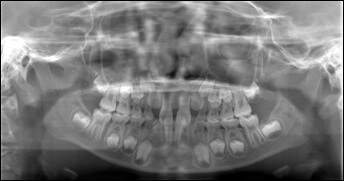

精密検査

問診票の記入、歯型、レントゲンおよび写真撮影、アゴの検査などの資料採得。

1時間のご予約。

全体矯正、部分矯正、補綴前矯正、歯科矯正用アンカースクリューを使用した矯正歯科治療など、年齢に関係なく行うことが可能です。矯正治療前に精密検査を実施し、患者様の希望にかなう治療ができるか十分な話し合いを行い、契約を結び、治療を開始します。